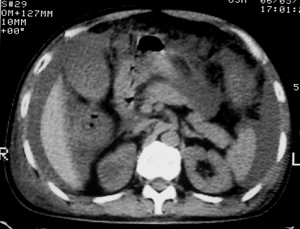

右侧肺癌术后:肝内可见多个大小不等的低密度结节影。腹腔及双侧胸腔大量积液。考虑:肺癌并胸膜及肝脏转移。

腹水,肝及右肾多发低密度影。考虑转移。

肝及右肾转移瘤,双侧胸水

右肾及肝内多发转移瘤,胸水。

1、右肺癌术后改变。2、双侧胸水、腹水。3、多发性肝囊肿,右侧肾囊肿。

目前转移或复发的依据不足,术后才一个月,个人认为还是让临床去判断,而且需结合术前常规检查,有无肝肾囊肿;另外有一个疑问:肝胃间隙内团状软组织影是胃食管交接区吗,胃腔太小了吧,有无手术史请楼主告知.